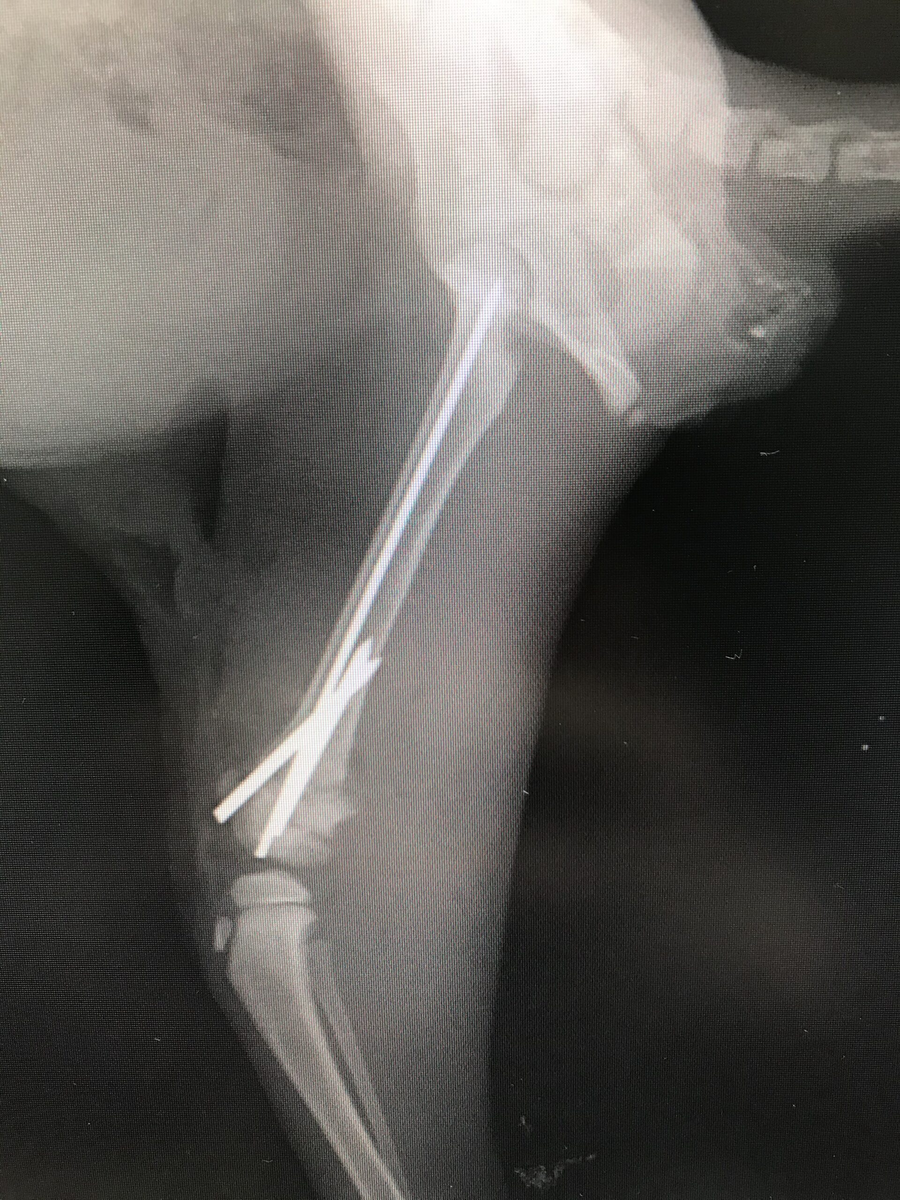

術後レントゲンです。

入院はほとんどの場合、4泊ほどです。

この子も術後の経過は良好で、退院時には多少かばいながらも着肢できていました。

術後1〜2ヶ月もするとかなり回復します。